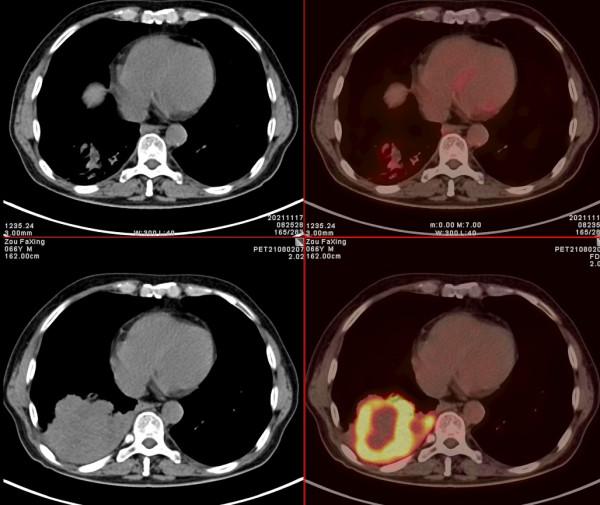

依據影像學分期,該患者後續進行了綜合治療:免疫+化療+靶向治療,其中化療3期,免疫治療2期及靶向治療。3個月後患者再次進行了PET/CT檢查,對治療效果進行了評估。2021年11月PET/CT檢查結果:

腫瘤病灶明顯縮小、實性成分明顯減少,腫瘤FDG代謝明顯減低,相鄰胸膜浸潤明顯改善,已經沒有胸水徵象。另外,全身其他部位未見明確轉移性病變。

複查後PET/CT診斷:右肺下肺癌綜合治療後,腫瘤病灶明顯縮小,FDG代謝明顯減低,相鄰胸膜未見高代謝病變,考慮腫瘤治療後療效顯著,僅少量腫瘤活性殘留。